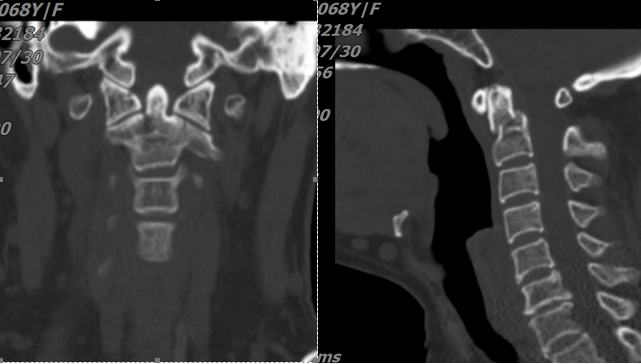

圖二:頸椎齒狀突骨折,骨折線前下往后上,屬于IIC型

寰樞椎在人體結(jié)構(gòu)中占有極為重要的地位,被稱作“生命禁區(qū)”。首先是因?yàn)?,寰椎屬于頸顱交界區(qū),此處有椎動脈和重要的生命中樞——延髓。其次,椎板間有粗大的靜脈叢、枕大神經(jīng),解剖結(jié)構(gòu)復(fù)雜,手術(shù)難度大、風(fēng)險(xiǎn)高,一旦發(fā)生意外會直接危及生命。再次,寰椎后弓進(jìn)釘點(diǎn)高度平均約4mm,而現(xiàn)在醫(yī)用螺釘直徑為3.5mm。最重要的是,以往的寰樞椎固定是在相對穩(wěn)定的骨質(zhì)上操作。本例手術(shù)需要在不穩(wěn)定的寰樞椎上鉆孔置釘。這些對手術(shù)的開展都是巨大的考驗(yàn)。

經(jīng)過充分的術(shù)前溝通和準(zhǔn)備,8月7日,陳志伸主任醫(yī)師、王慶敏副主任醫(yī)師及其手術(shù)團(tuán)隊(duì)依靠精湛的技術(shù),歷時2小時,成功為患者實(shí)施了“頸后路寰樞椎釘棒內(nèi)固定+植骨融合術(shù)”。術(shù)后第1天患者可以在支具保護(hù)下坐起,術(shù)后3天可獨(dú)立下地行走!